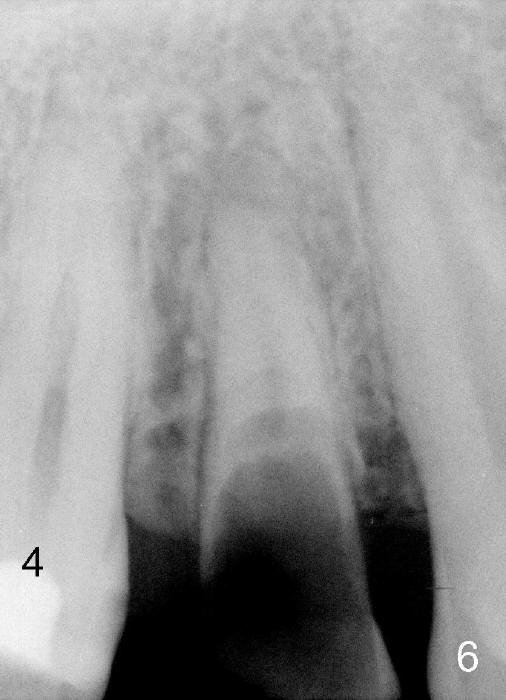

A 25-year-old black man has poor dentition. The tooth #5 is non-salvageable (Fig.1-6). Although the 1st bicuspids belong to the posterior teeth, anterior sensor holders should be used to show the sinus floor (Fig.1,2: ^). In contrast, PAs in Fig.3,6 (trimmed mesiodistally) are taken with posterior sensor holders; the sinus floor is out of view.

A long implant will be placed (possible 4.5x20 mm, Fig.2). A typical 1st bicuspid has 2 canals. In this case, there are most likely two roots (Fig.3): buccal (Fig.4 green dashed line) and lingual (Fig.5 pink dashed line).